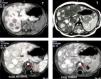

Al mes de edad las ecografías transfontanelar y cardíaca fueron normales y una ecografía renal confirmó la existencia de discreta ectasia piélica. Durante la realización de este último examen, se verificó la existencia de múltiples nódulos hepáticos hipoecogénicos, dispersos por ambos lóbulos, la mayoría de ellos de cerca de 2,5cm de diámetro (fig. 1); el estudio con modo Doppler mostró que estos nódulos estaban francamente vascularizados; los conductos biliares intrahepáticos y extrahepáticos tenían el calibre preservado; las venas suprahepáticas y la vena porta tenían dimensiones y flujo normales; bazo sin alteraciones; ausencia de adenomegalias o masas en el retroperitoneo. La alfa-fetoproteína sérica estaba elevada (441,5ng/ml; N < 1,5); hemograma y enzimas hepáticas normales; el estudio de coagulación era normal; catecolaminas y sus derivados en orina no presentaban alteraciones.

El paciente fue visitado por primera vez en la consulta de hepatología a los 4 meses de edad. Estaba asintomático y el examen físico era igual que el descrito anteriormente. La resonancia magnética (RM) abdominal mostró la presencia de múltiples nódulos hepáticos hiperecogénicos en T2. Después de la inyección de gadolinium fue posible confirmar la naturaleza extremamente vascularizada de estos nódulos (fase arterial, fase venosa y fase tardía) (fig. 2); ausencia de masas suprarrenales y retroperitoneales.